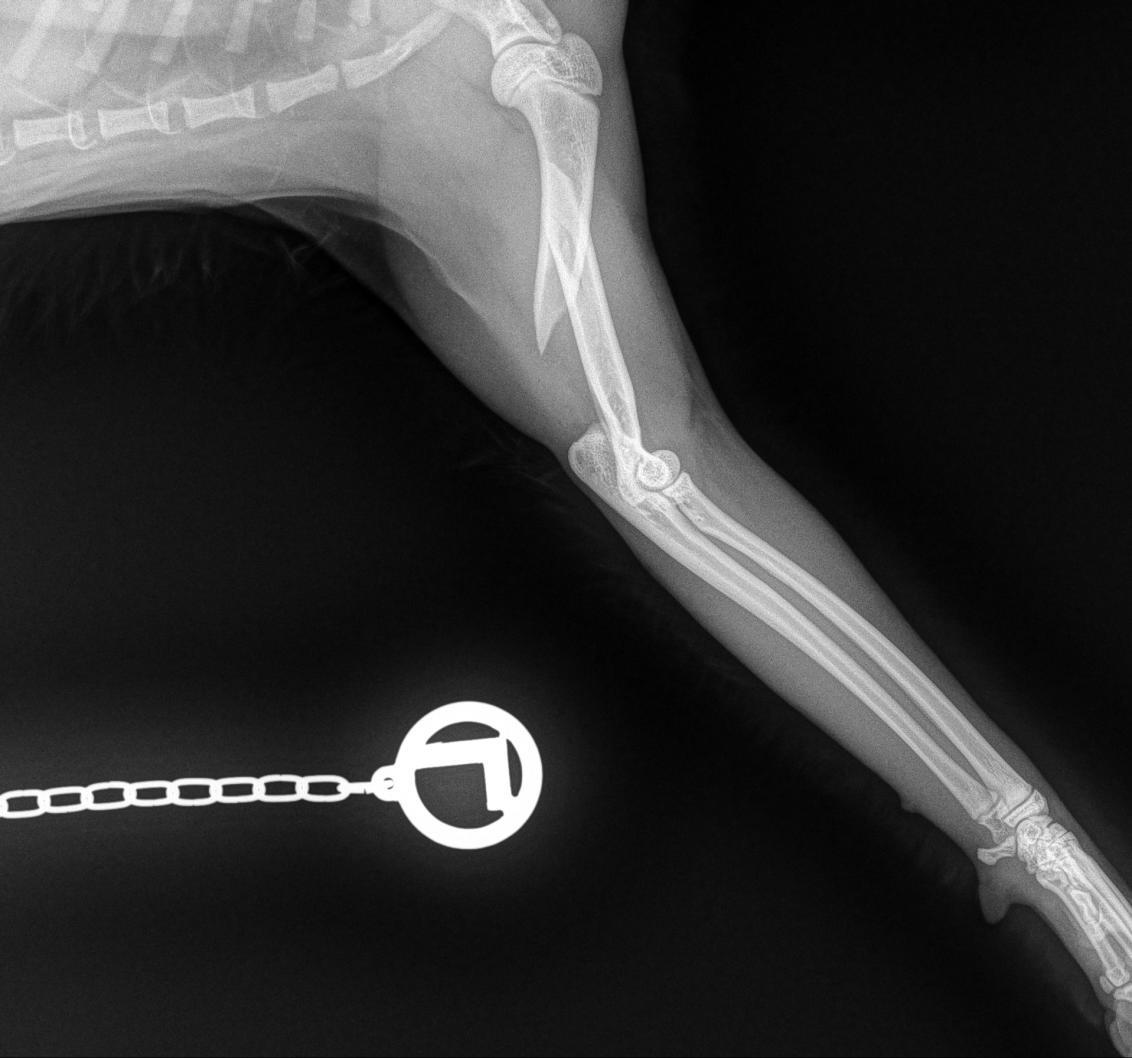

Day 1: He had to fix a humerus spiral fracture (left) with a LeiLOX bridge plate. Furthermore, he diagnosed a femur transverse fracture. Dr. Sonntag then used a 7-hole LeiLOX plate to repair this fracture, and do several emergency soft tissue surgeries.

(Surgery time: 1:15 hours)